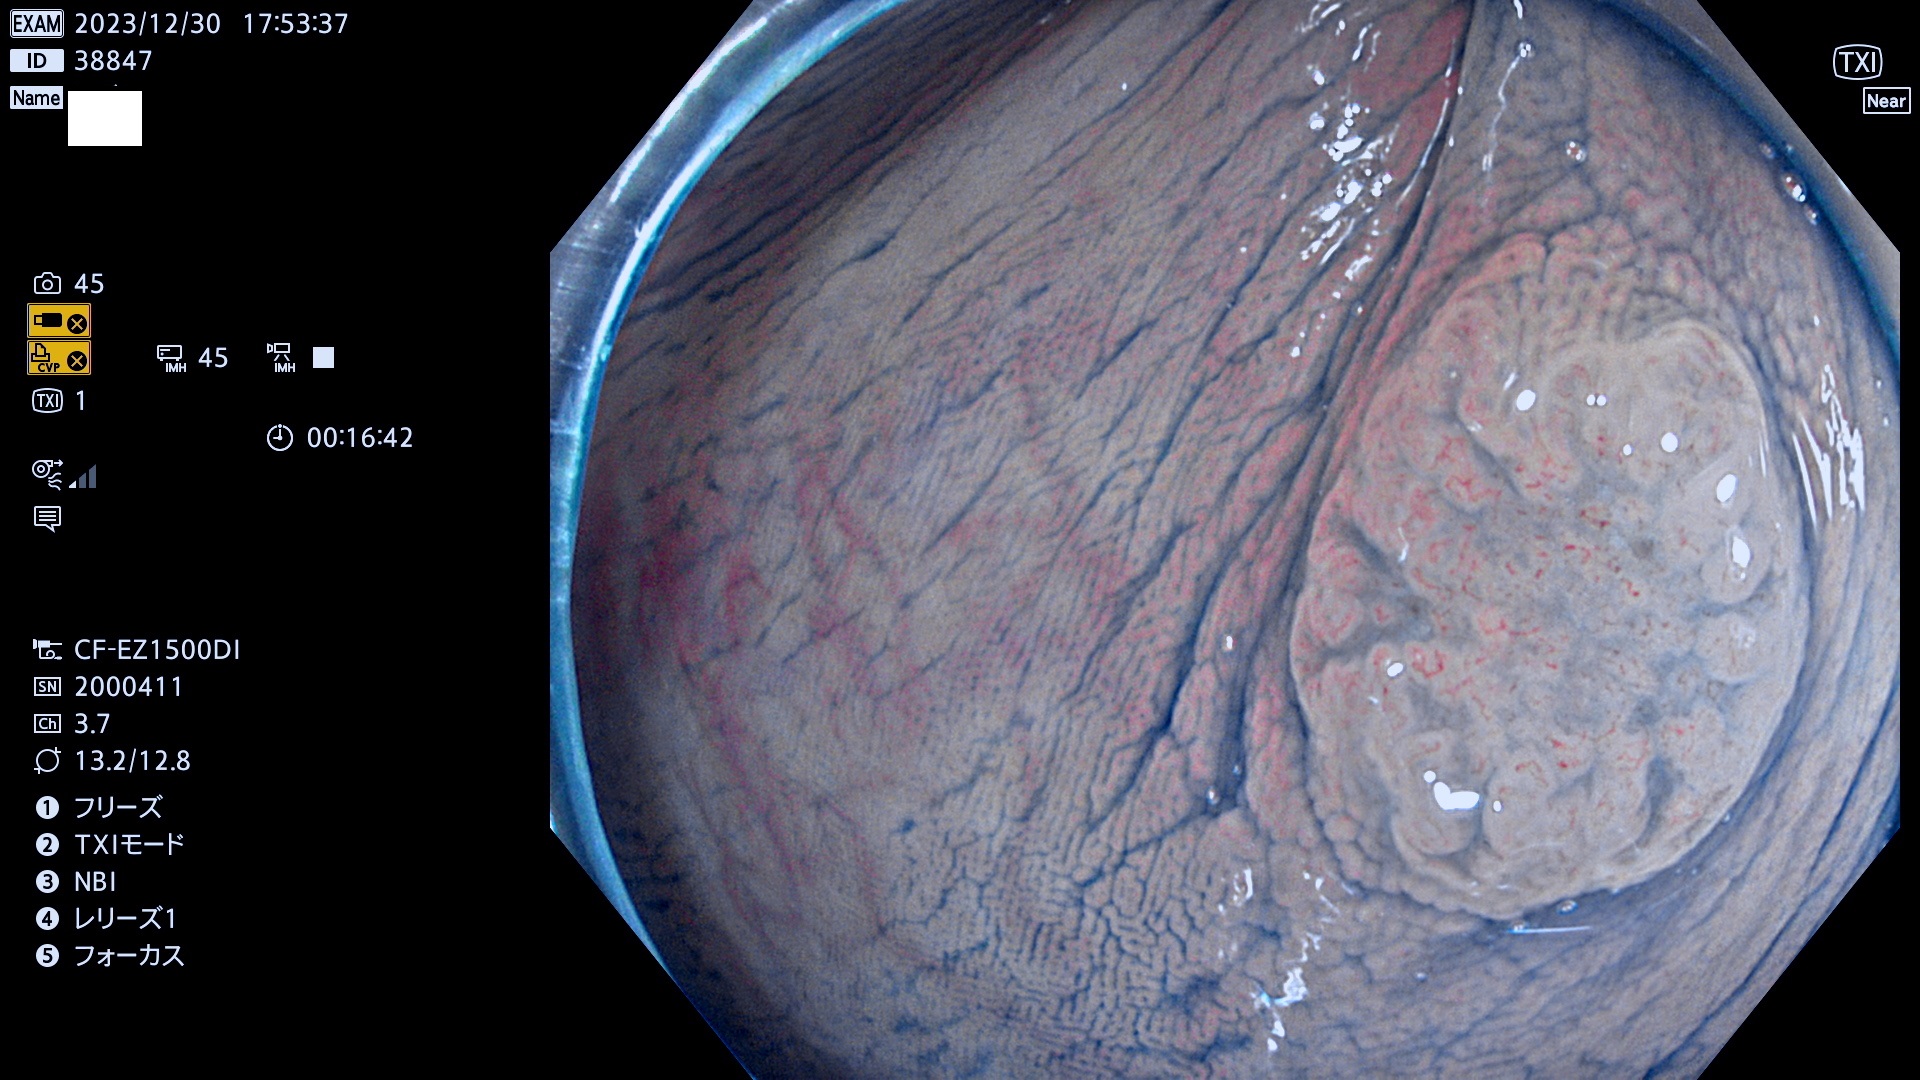

表面型腺腫(Flat Adenoma)の中で、完全に平坦な物をUb、陥凹している物をUcと呼びます。平坦隆起型(Ua)よりも、発見が難しく危険な病変です。

専門的)Uc=De Novo癌? 内視鏡の解像度が低かった時代、このような説もありました。しかし今日の高精度内視鏡では良性の微小なUc型腺腫が日常的に見つかります。私見ですが「Ucこそが多段階発癌(Adenoma-Carcinoma Sequence)のMain Route」と考えます。

毎週の検査(木・金・土・日)に発見されたUb、Uc型・腺腫を、その週の日曜の夜にUPし1週間、提示します。

抽出の対象期間 2023年12月28日(木)〜12月31(日)の4日間(48件の検査)7件